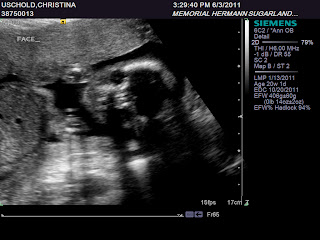

GIRL!!! We are very blessed that we have another healthy girl on the way. We are very excited that Reese will have a sister and a best friend. I can hear the squeals of laughter at slumber parties in years to come. Daddy is very outnumbered! We can't wait to meet our baby girl in October. She was very active today and we got some great shots!!